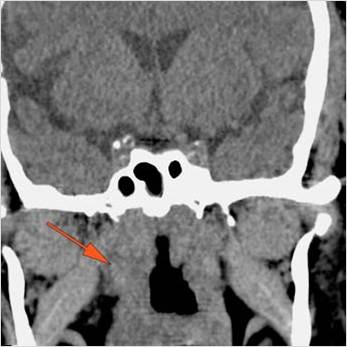

There is evidence of thrombus, thrombophlebitis or other occlusive or inflammatory process of the cavernous sinus.